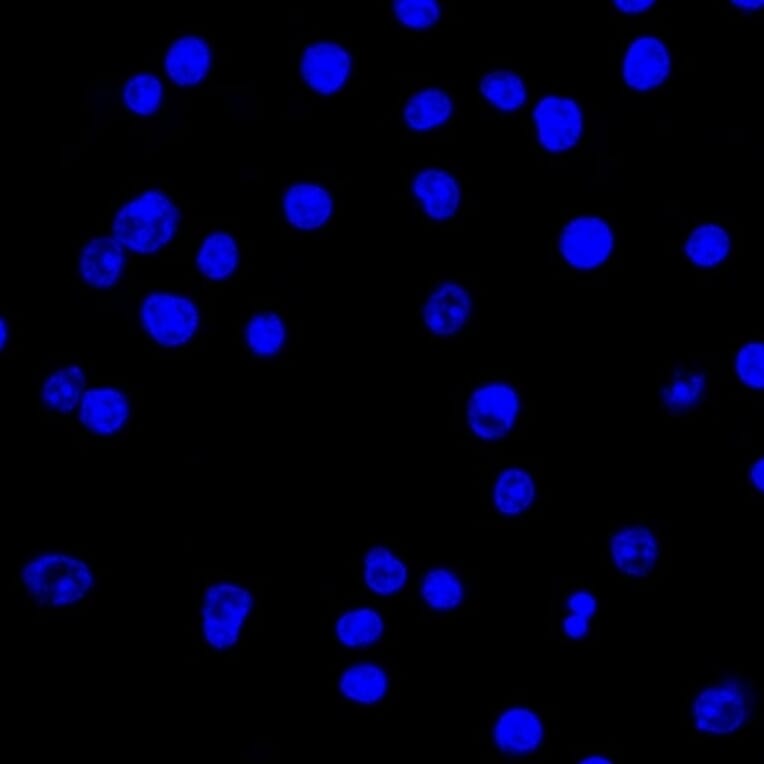

Mouse monoclonal [LcN-2] antibody to Lambda Light Chain for Flow Cytometry, IF, WB and IHC-P.

Flow Cytometry, IF, WB, IHC-P

Flow Cytometry: 1-2 µg/million cells, IF: 1-2 µg/ml, WB: 1-2 µg/ml, IHC-P: 0.25-0.5 µg/ml